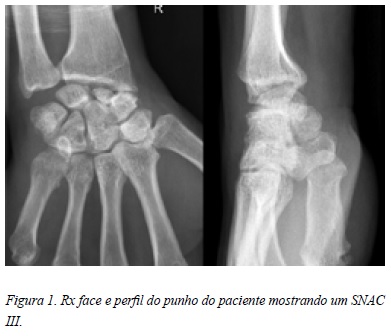

Radiologicamente apresentava uma pseudoartrose do escafóide associado a artrose radioescafoideia e escafocapitato, classificando-se como SNAC III (Figura 1).